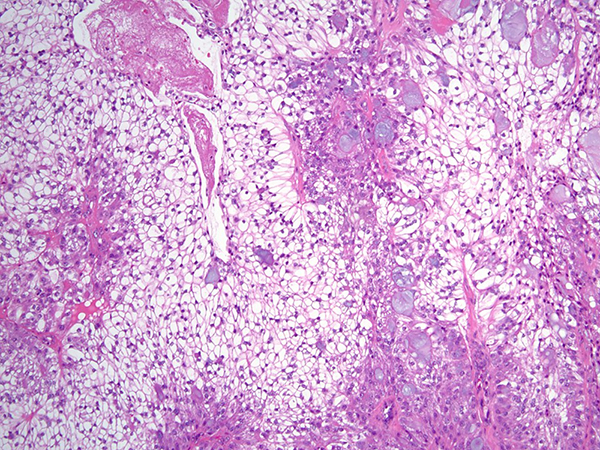

Clinical History: A 28-year-old man with progressively worsening dyspnea on exertion was noted on chest imaging to have a near-completely-obstructing endoluminal lesion in the distal trachea. He is a never smoker and endorsed no significant past medical history. Bronchoscopy confirmed the presence of a lobulated, partially-obstructing endotracheal lesion (Figure 1). A rigid bronchoscope was used to core out the lesion and electrocautery was applied to the base for tissue ablation and hemostasis. Histologic sections (Figures 2-5; H&E) demonstrated a circumscribed epithelial neoplasm composed of expansile nests of clear cells with only mild cytologic atypia. The clear cells were admixed peripherally with slightly larger-appearing cells characterized by eosinophilic cytoplasm and occasional small central nucleoli. Scattered throughout the tumor were collections of mucin-containing cells with occasional small cysts. A somewhat arborizing vascular network with some hyaline-appearing fibrosis was also present. Mitoses were not apparent and neither keratinization nor necrosis were identified. The over lying tracheal epithelium demonstrated early evidence of squamous metaplasia, but no overt cytologic atypia. Immunohistochemical stains (Figure 6) demonstrated the lesional cells to be diffusely CK7 positive with focal collections of cells demonstrating p40 and CK5/6 positivity. The lesional cells were TTF-1 negative.

The vast majority of recently published cases of PMEC harbor a recurrent t (11; 19) (q21; p13) translocation, resulting in a CRTC1-MAML2 fusion gene. In this case, fluorescence in-situ hybridization using probes to detect rearrangements of the MAML2 gene region was performed and reported as positive for rearrangement. Such rearrangements have been identified in both low and high-grade PMEC; though, their role as a prognostic indicator is not entirely clear. Immunohistochemically, PMECs are pancytokeratin, CK7, CK5/6, and p63/p40 positive. PMECs are TTF-1 and Napsin A negative. The presence of mucus cells and the MAML2 rearrangement effectively exclude the possibility of metastatic renal cell carcinoma. Hyalinizing clear cell carcinoma (HCCC) is also characterized by the presence of mucus cells; however, both salivary gland and pulmonary HCCC have been demonstrated to harbor EWSR1 rearrangements, not MAML2 rearrangements. Perivascular epithelioid cell neoplasms (PEComas) also lack MAML2 rearrangement and are generally positive for melanoma markers, smooth muscle actin, and desmin.

For this case, a final diagnosis of mucoepidermoid carcinoma, favor low-grade was rendered. Most PMECs are low-grade, and with complete surgical resection have an excellent prognosis. High-grade PMEC portends a prognosis similar to other non-small lung cancers. This patient subsequently underwent tracheal resection with lymph node dissection that revealed no residual disease or evidence of metastasis.